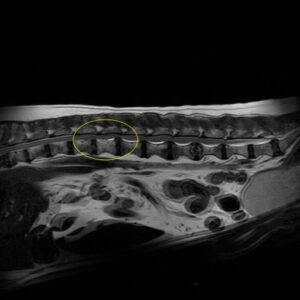

CT/MRI検査

CTの場合は造影剤を用いることが多いですが、CTだけでは診断ができない場合もあります。MRI検査であれば椎間板ヘルニアを確定診断することが可能であり、そのほかの病気を見つけることもできます。